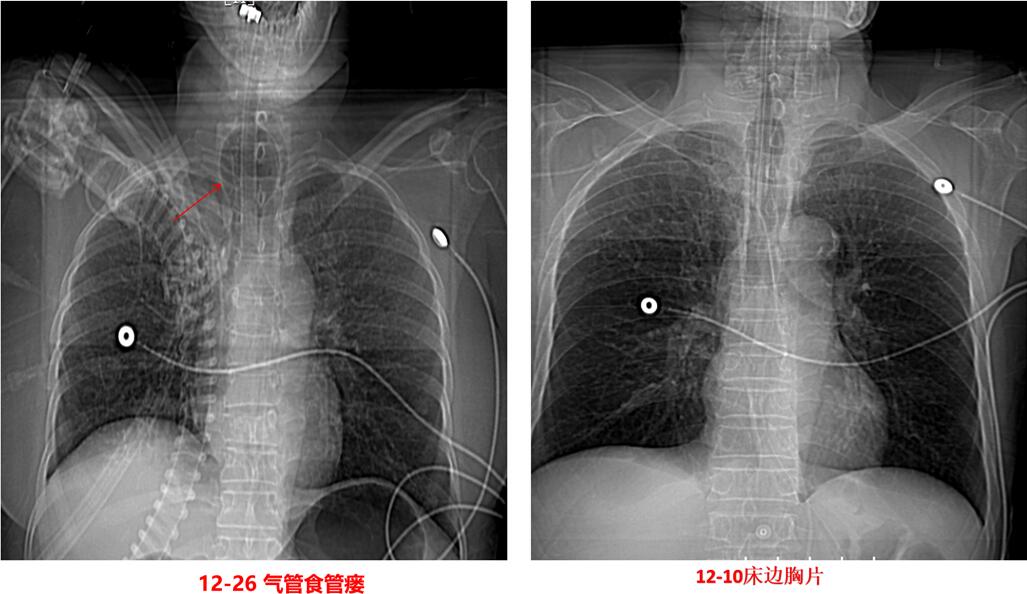

12月26日查房时可听到患者喉部有“呼噜声”,并再次出现腹胀,呼吸机报警潮气量低,分钟通气量仅3.0-3.5L,此时上级医师考虑可能出现了气管食管瘘。当时检查气管插管气囊压力,比鼻尖还软一点,可拿气囊测压表一测,大家都惊呆了,测压器显示此刻压力达到了80.3cmH2O!这远远超过了正常压力范围。为证实气管食管瘘,当天下午我们就给患者做了床边胃镜及胸部CT。

胃镜下清晰可见食管壁有一巨大的破口,气囊和气管插管“突破”重重阻碍到食管了。胸部CT和定位片都可明显看出来。

图2 发生气管食管瘘的胸片与之前的胸片对比